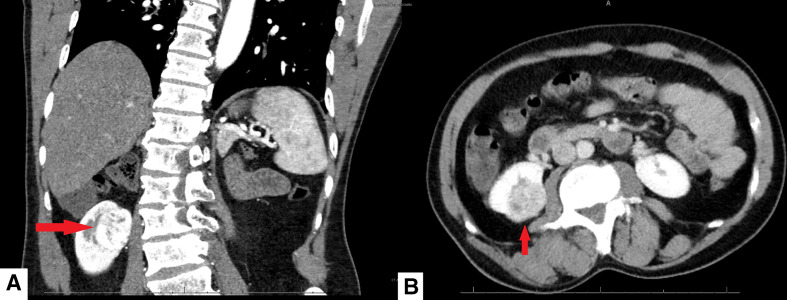

The selected abdominal CECT images below demonstrate the same lesion noted above, after a 2-year interval. A heterogeneously enhancing mass in the upper pole of the right kidney measuring 2.7×3.7 cm with characteristics concerning for renal cell cancer is demonstrated. The measurement of this lesion is more likely to be accurate using CT scan instead of ultrasonography although it is unlikely significant interval growth occurred between acquisition of these images as renal cell carcinomas tend to grow between 2 and 3 mm per year (figure 2).

Figure 2.

Contrast-enhanced CT scan showing a heterogeneously enhancing mass in the right upper pole moiety measuring 2.7×3.7 cm (arrow) in coronal (A) and axial (B) projections.